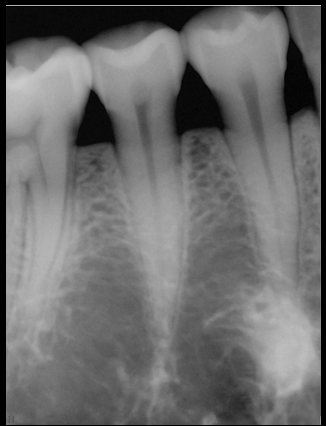

CR/DR 牙齿分割阶段记录

当前进展

- 完成了 CR/DR 牙齿相关分割训练

相关测试

遇到的问题

- 训练过程中出现过 mask 下移问题

- 部分结果会出现 box 填充异常

- mask 边缘仍然有比较明显的锯齿感